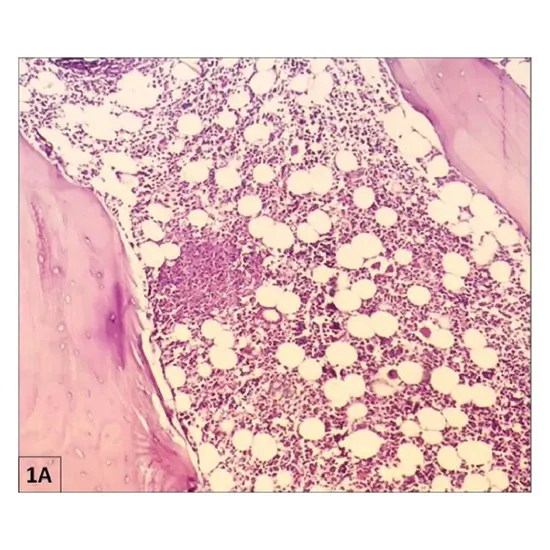

Decalcified sections are used to examine the bone marrow and to diagnose infections, tumours, and other conditions. The samples may come from dissected amputation specimens, iliac crest trephines, or bone fragments taken out during surgery (such femoral heads)

Bone Marrow Trephine Biopsy Specimen Sections Staining. Haematoxylin and eosin (H&E) and reticulin should be routinely stained on bone marrow sections using a silver impregnation technique. Romanowsky dyes like May-Grünwald-Giemsa and Perls' reaction can also be used to stain sections.